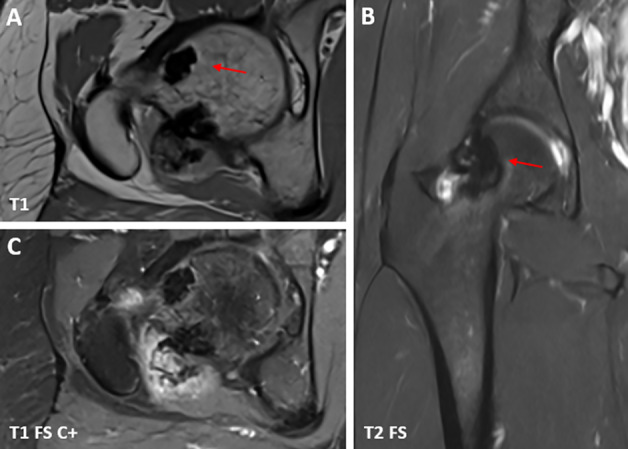

教学要点Melorheostosis 是一种罕见的硬化性骨发育不良,其特点是骨皮质周围和/或骨皮质内侧硬化,导致骨轮廓起伏增厚,类似于 "滴落的蜡烛蜡"。

Teaching point: Melorheostosis is a rare sclerosing bone dysplasia, characterized by sclerosis at the periosteal and/or endosteal side of the cortex, causing undulating thickening of the bony contour resembling "dripping candle wax."